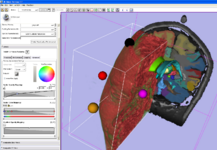

Implicit Slice Widget: An interactive tool for specifying oblique views (part of the VTK widget family).